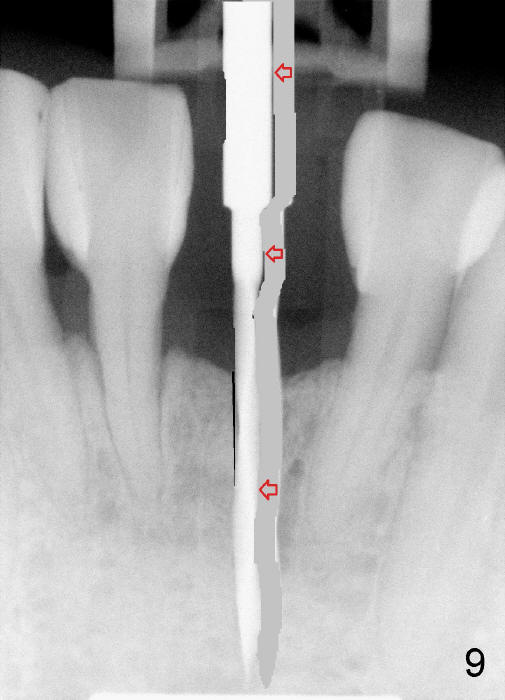

To place the implant correctly, the preop PA should be studied carefully to find the divergence of the roots of the neighboring teeth (Fig.1).  The depth of the initial osteotomy should be shorter, for example, 11 mm instead of 14 mm.  Once the trajectory is found to be corrected, an incision should be made; the osteotomy is to be overcorrected with Lindermann bur (Fig.8 black); the whole osteotomy is changed with proper angulation (Fig.9 arrows).